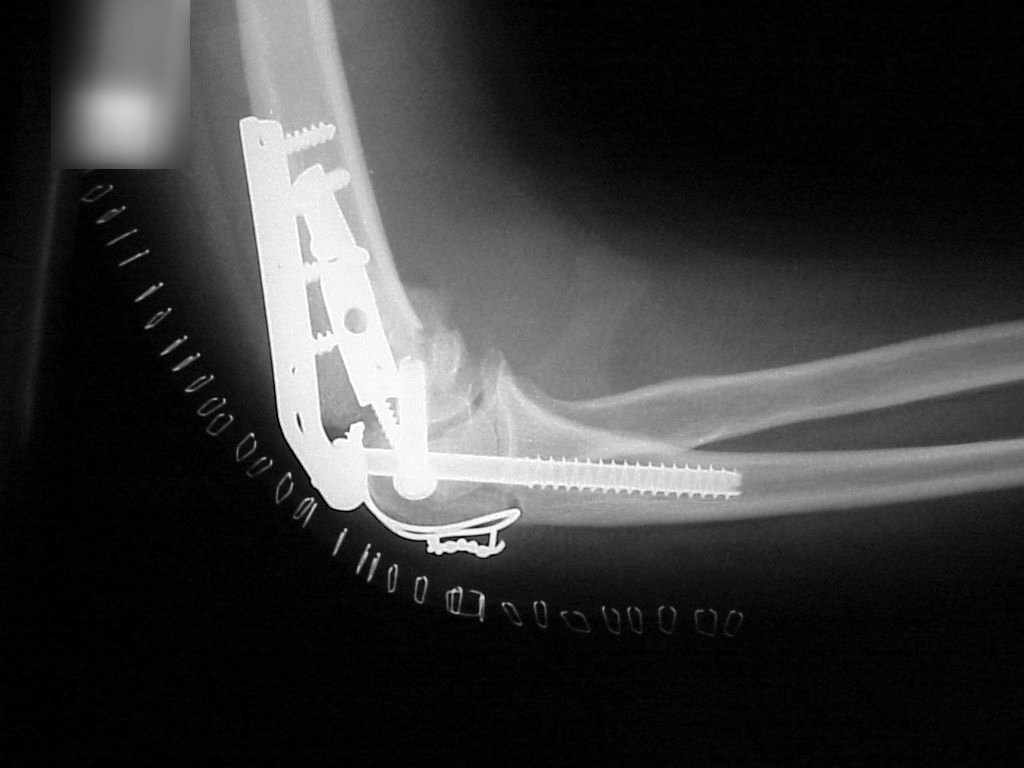

Films on arrival, one week after surgery. Neurovascular exam is normal. Early loss of fixation.

Click for larger image